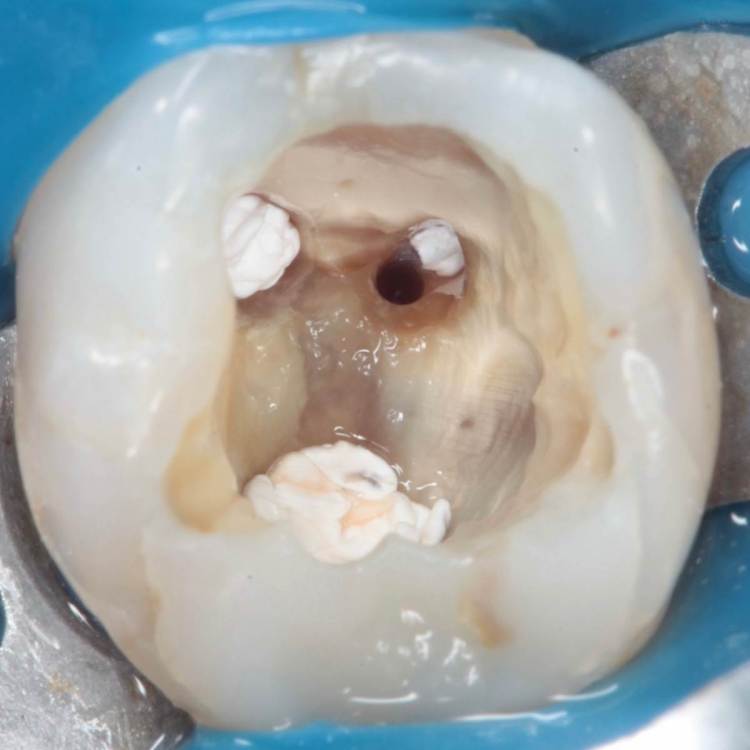

Перфорация закрыта триоксиденом, очень классный материал, и главное – наш!))

Для того чтобы при паковке триокси не провалился в каналы, они закрываются фторопластом